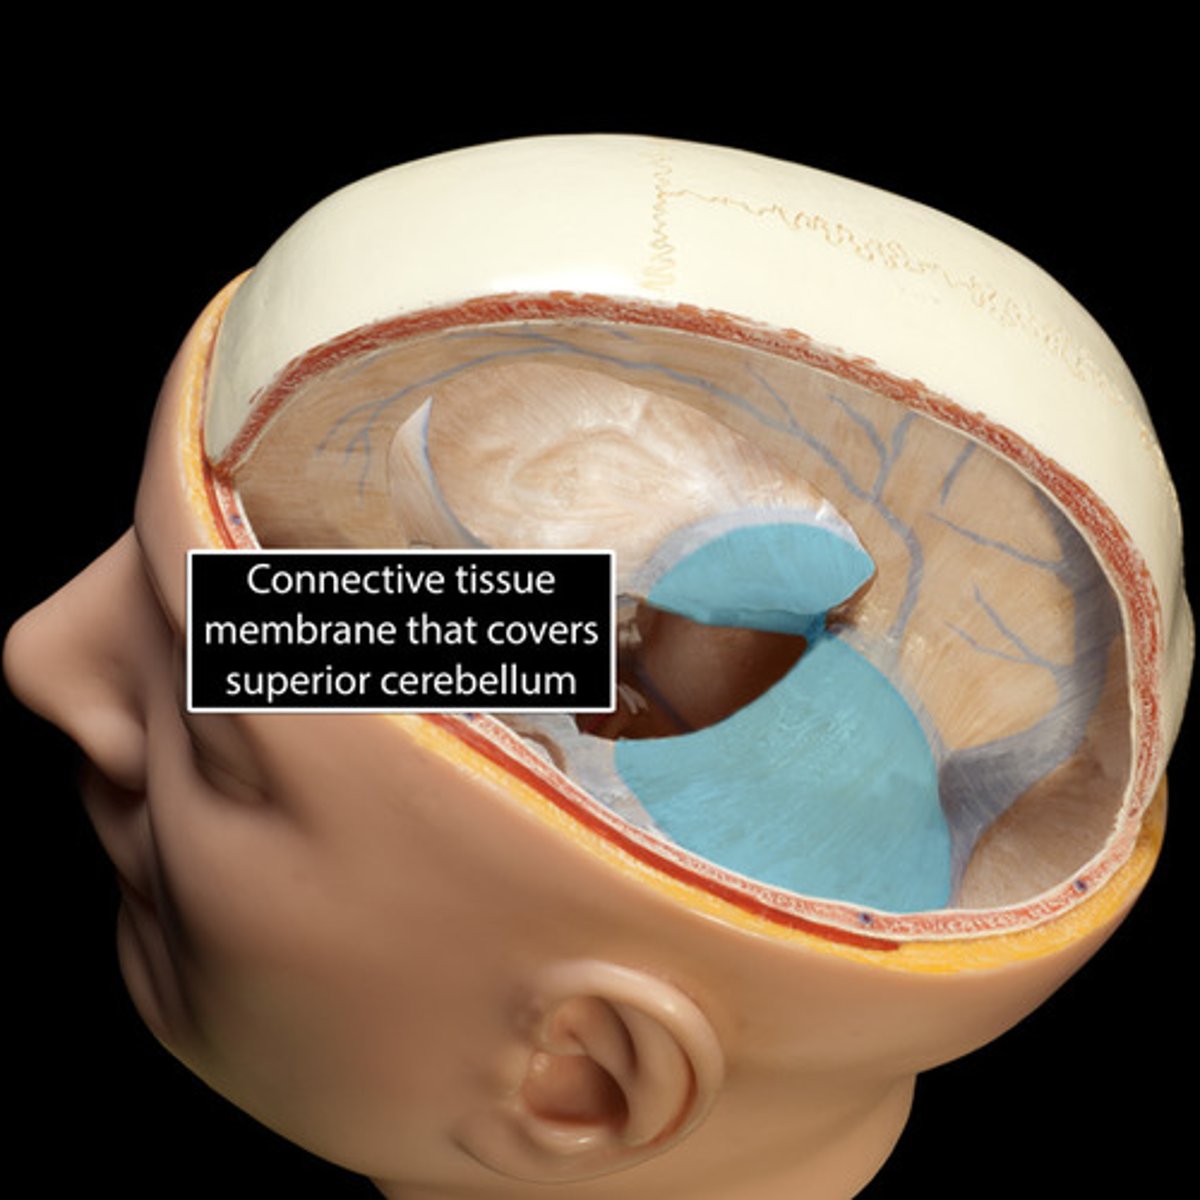

tentorium cerebelli

between cerebrum and cerebellum